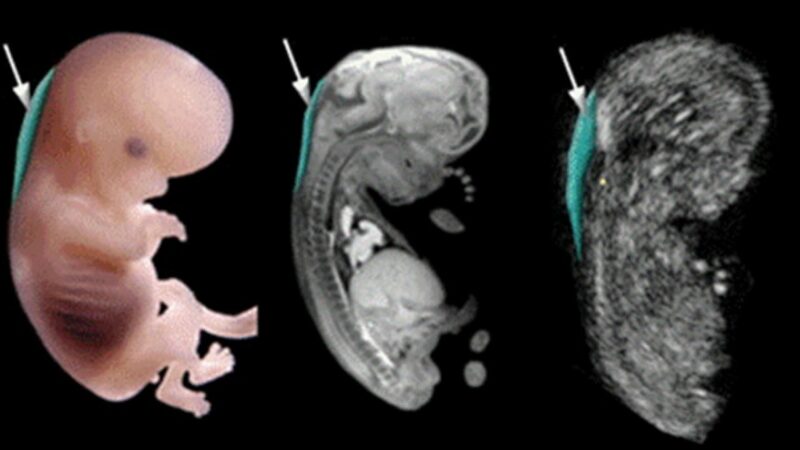

Siêu âm là phương pháp chẩn đoán hình ảnh không xâm lấn, sử dụng sóng âm thanh tần số cao xuyên qua cơ thể và phản xạ trở lại chuyển thành những hình ảnh được hiển thị trên màn hình, giúp bác sĩ chuyên khoa theo dõi và đánh giá chi tiết cấu trúc bên trong.

Siêu âm cho phép bác sĩ kiểm tra vị trí lẫn sự phát triển của thai nhi theo độ tuổi. Nếu có bất kỳ sự bất thường hoặc sai lệch so với tiêu chuẩn, bác sĩ sẽ kịp thời tư vấn thai phụ cách xử lý.

Siêu âm giúp bác sĩ kiểm tra tỉ mỉ sự phát triển của thai nhi, đảm bảo phát hiện sớm các bất thường để can thiệp kịp thời.